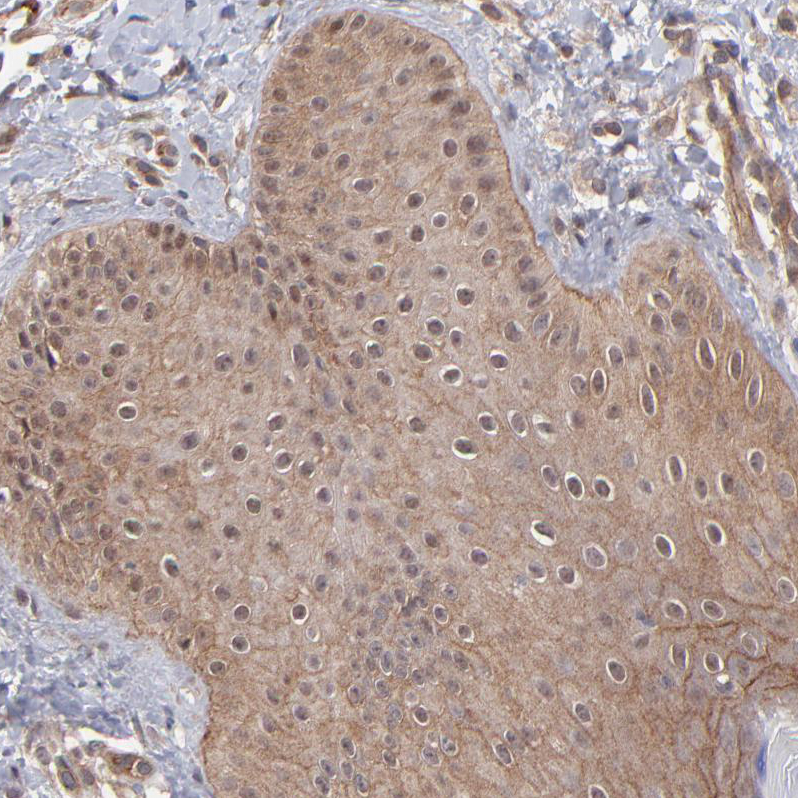

Immunohistochemical staining of human rectum shows strong cytoplasmic positivity in glandular cells.